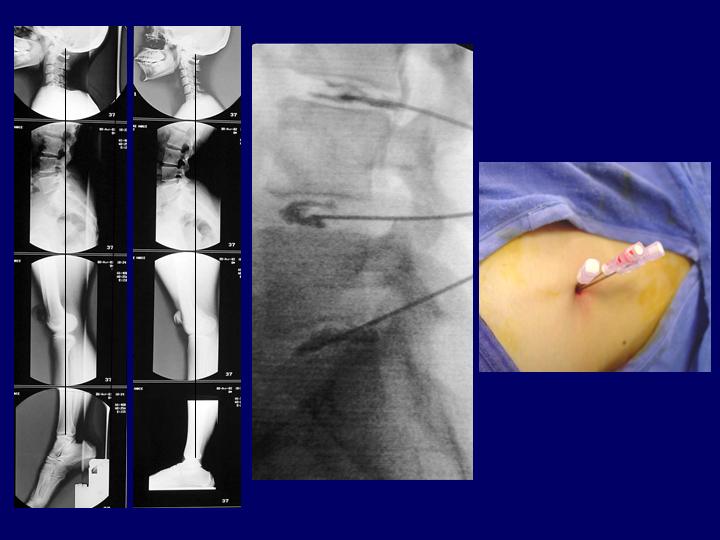

Hernias Discales